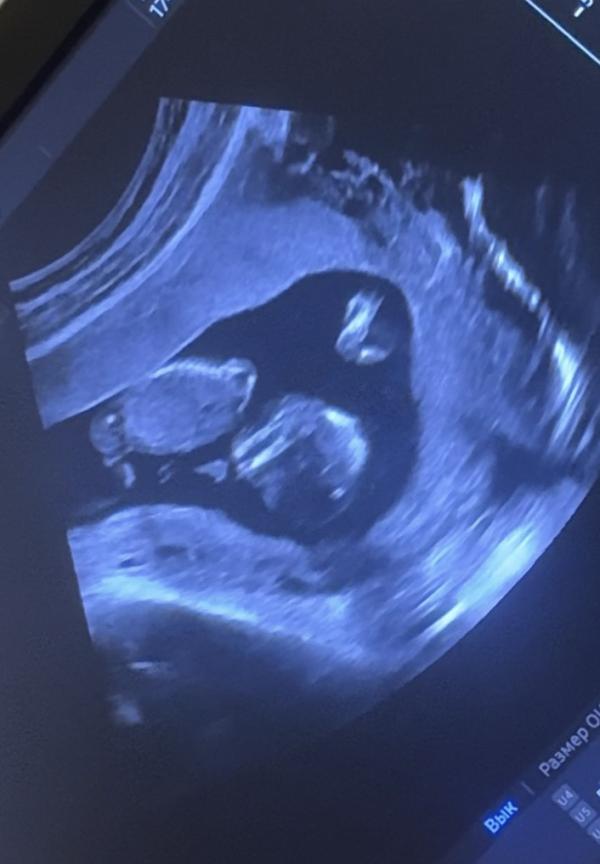

Малыши лежат как в гороскопе знак Рыбы)

По 6 см примерно(на прошлом узи в 11 нед. были по 4,5) один чуть больше другого. Послушали сердцебиение (тх тх тх тх тх тх), все хорошо, все по сроку.